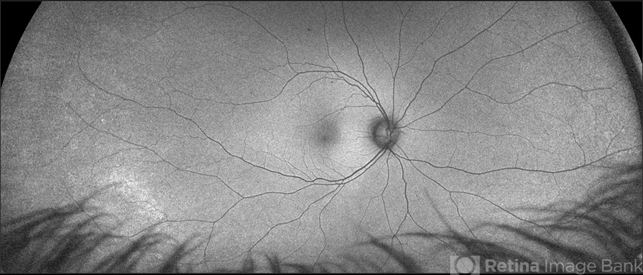

- Tractional Vs Combined TractionalRhegmatogenous Retinal Detachment with active Neovascularization

- tractional retinal detachment, combined retinal detachment

Scanning laser ophthalmoscope

Optos California - Description

- 47-year-old African American, with history of diabetes mellitus of unknown duration and control, was referred for initial evaluation for conjunctival laceration in his left eye, following accidental finger nail injury, 6 days prior to presentation. - On exam, his vision was 20/50 OD and Bare HM/ LP OS. - Fundus color photos OD: No significant pathology, aside from attenuated vasculature OS: Chronic, Mac-Off, almost closed funnel tractional vs combined tractional/rhegmatogenous retinal detachment with large neovascularization (NVE) superiorly, detached ghost vessels, mild fresh vitreous hemorrhage, sub-retinal bands and inferior white vitreous debris from old hemorrhage (Not shown) - FA OD: No significant pathology aside from possible mild capillary non-perfusion in the extreme periphery, attenuated vasculature and possible tiny microaneurysms, nasally. OS: Extensive, wide spread capillary non- perfusion (correlate w/ detached ghost vessels on color photos), and leakage from the NVE. - B/L Carotid Duplex was recommended due to the striking asymmetry in pathology with unknown medical history, diabetes duration and control, etc (even in absence of any signs suggestive of possible ocular ischemic syndrome OD)